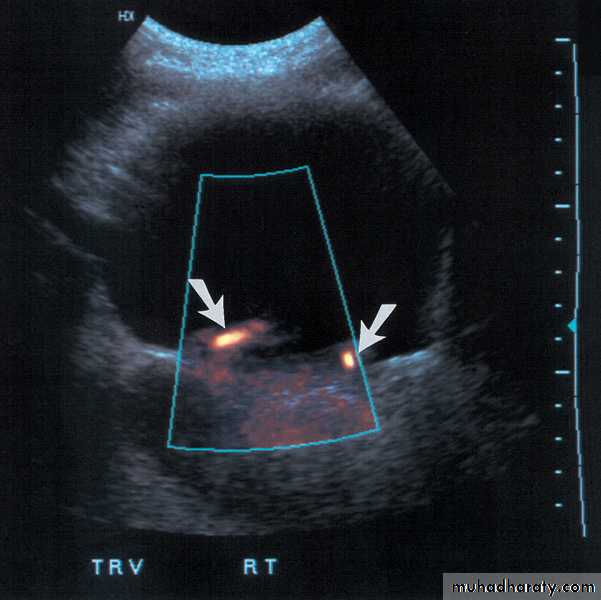

Color-flow Doppler techniques - measuring blood flow